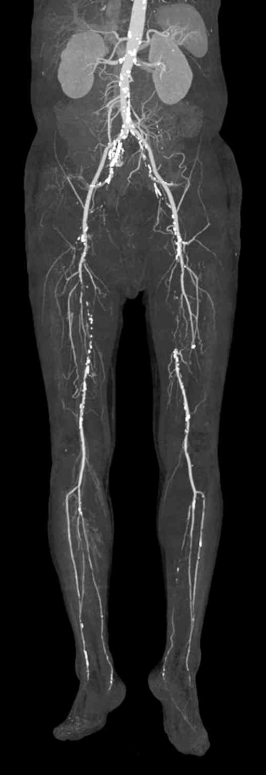

75세 남자가 6개월 전부터 다리가 아파서 병원에 왔다. 50 m정도를 걸으면 양쪽 종아리가 아프고 2개월 전부터 점점 심해졌다고 한다. 30갑•년의 흡연자이다. 20년 전부터 경구 혈당강하제를 복용하고 있다. 혈압 120/70 mmHg, 맥박80회/분, 호흡 20회/분, 체온 36.5°C이다. 검사 결과는 다음과 같다. 컴퓨터단층촬영 혈관조영 사진이다. 진단은?

CTA: Abdominal aorta diffuse calcification, Rt. SFA segmental occlusion, Lt. SFA complete occlusion

Imp: 말초동맥질환(peripheral artery disease, PAD, 폐쇄동맥경화증, arteriosclerosis obliterans)

고령, 흡연력, 당뇨병이 있는 환자에서 혈관성 파행 증상이 확인되고 낮은 ABI와 이에 부합하는 CTA상 혈관 폐색 소견이 확인되므로 PAD로 진단한다.

• ABI를 측정한 결과 양측 모두 ABI < 0.9로 양 하지의 PAD를 의심할 수 있다. 따라서 PAD에 대한 진단으로 초음파 도플러 스캔(duplex scan)이나 혈관조영술을 시행하여 재관류 치료 전 세부 치료방침을 수립하여야 한다.

• 해당 증례에서는 CT 혈관조영술을 시행하였으며 bilateral superficial femoral a. occlusion이 저명하게 관찰된다.

• 따라서 병력과 영상 소견을 종합하여 볼 때 PAD로 진단할 수 있다.